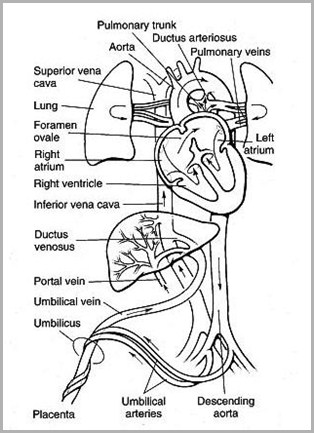

Placenta umbilical vein(ligamentum teres) hepatic sinusoid & ductusvenosus (ligamentumvenosum) portal vein IVC right atrium foramen ovale leftatrium left ventricle aorta systemiccirculation umbilicalarteries placenta

Fetal Circulation

From the umbilicus,umbilical vein passescephalad, slightly toright

Joins the left branch ofthe portal vein

The ductus venosusarises from the pointwhere the UV joins theleft portal vein

Ductus venosus entersIVC

UVC should be justabove diaphragm whereIVC enters RA (T8-T9)

Umbilical arteriesare directcontinuation ofinternal iliacarteries

UAC will usuallyenter aorta viainternal iliac artery

UAC should thenpass up aorta,above diaphragm,between T6 and T9